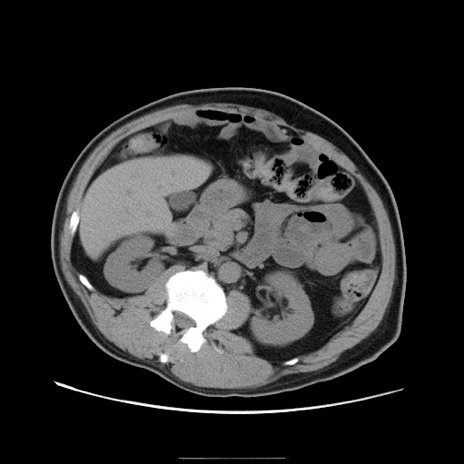

冠状断像

【症例】50歳代男性

【主訴】腹痛

【現病歴】AVMからの被殻出血のため回復期リハ病棟入院中。 本日午後3時頃急に下腹部痛が出現した。

【既往歴】AVM、被殻出血、虫垂炎、高血圧

【身体所見】意識晴明、左半身不全麻痺、会話の理解は良好、36.5°C、腹部:膨隆、全体に板状硬、下腹部正中に圧痛点あり、反跳痛-、筋性防御不明、右下腹部にope scar

【データ】WBC 9400、CRP 0.06